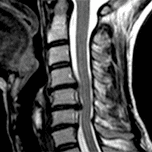

BEZPŁATNE PORADY MEDYCZNE ONLINE, W ZAKRESIE CHOROBY FILUM: Syndrom Arnolda Chiari I, Idiopatyczna jamistość rdzenia, Skolioza idiopatyczna, Płaskopodstawie, Wgłobienie obrotnika do jamy czaszki, Odchylenie kręgu obrotowego, Wygięcie pnia mózgu.

Jesteśmy międzynarodowym centrum medycznym, świadczącym obsługę w 16 językach, bez oddziałów, z siedzibą w Barcelonie- HISZPANIA. Leczymy przyczynę Syndromu Arnolda Chiari, Syringomielii idiopatycznej oraz Skoliozy idiopatycznej – oraz powiązanych schorzeń– proponując inne podejście: małoinwazyjny zabieg chirurgiczny z doskonałymi wynikami, szybką rekonwalescencją i bez znaczących powikłań.

Zespół Arnolda-Chiariego typu I, skolioza i idiopatyczna syringomielia.